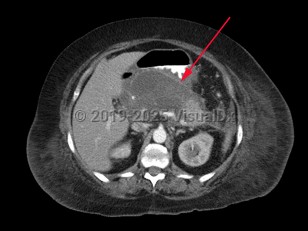

Pancreatic pseudocyst

A pancreatic pseudocyst is a localized, mature, fluid-filled collection, sometimes with debris, located outside of the pancreas. It has a nonepithelialized wall of fibrous and granulation tissue, with no necrosis present. Pancreatic pseudocysts typically appear at least 4 weeks after an episode of acute pancreatitis or blunt or penetrating pancreatic trauma. Pancreatic pseudocysts can also form in patients with chronic pancreatitis if there is an acute exacerbation of the underlying pancreatitis. Ten percent of patients with chronic pancreatitis will develop pseudocysts. Pancreatic pseudocysts are more commonly diagnosed in males.

Pancreatic pseudocyst